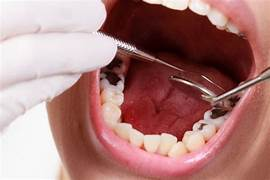

- Quan sát trực tiếp: Nha sĩ quan sát trực tiếp cung của bệnh nhân để đánh giá dạng hình, sự sắp xếp của các loại răng và các loại bất thường khác.